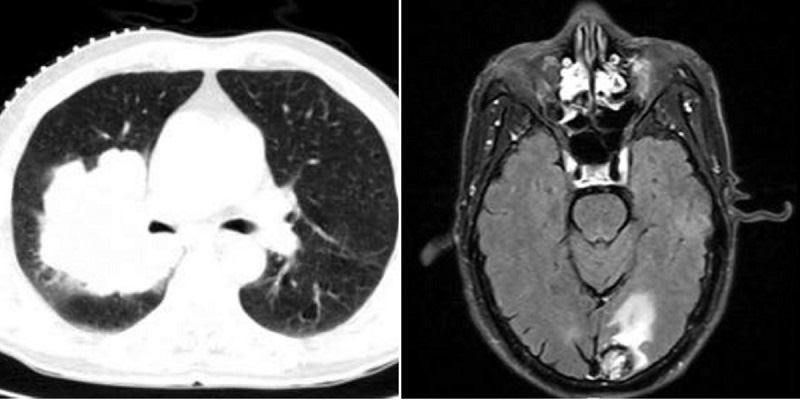

2016年7月,李先生反复出现咳嗽咳痰一个月,期间吃多种化痰止咳药均无效果,还出现痰中夹带血丝、时而胸闷等情况,李先生急忙到当地医院进行进一步检查,而结果却不尽人意,李先生被确诊为支气管肺癌,并且已出现骨、脑转移,免疫组化提示:李先生的癌细胞为分化较差的癌,倾向于腺癌并鳞样表型(分化差的癌指的是恶性肿瘤的发展状态,也就是说此种类型的癌细胞恶性程度较高,相对来说,是指肿瘤的发展进程较快,通常情况下,这类的恶性肿瘤病人大多会很快进入到肿瘤晚期。)

·2016年8月26日,侯主任为李先生行脑转移瘤射波刀治疗。

·2016年9月7日,侯主任为李先生行肺癌射波刀治疗。

·2017年2月,李先生返回瑞康医院肿瘤科二区进行复查,复查结果提示:病灶较前缩小,脑转移瘤消失。